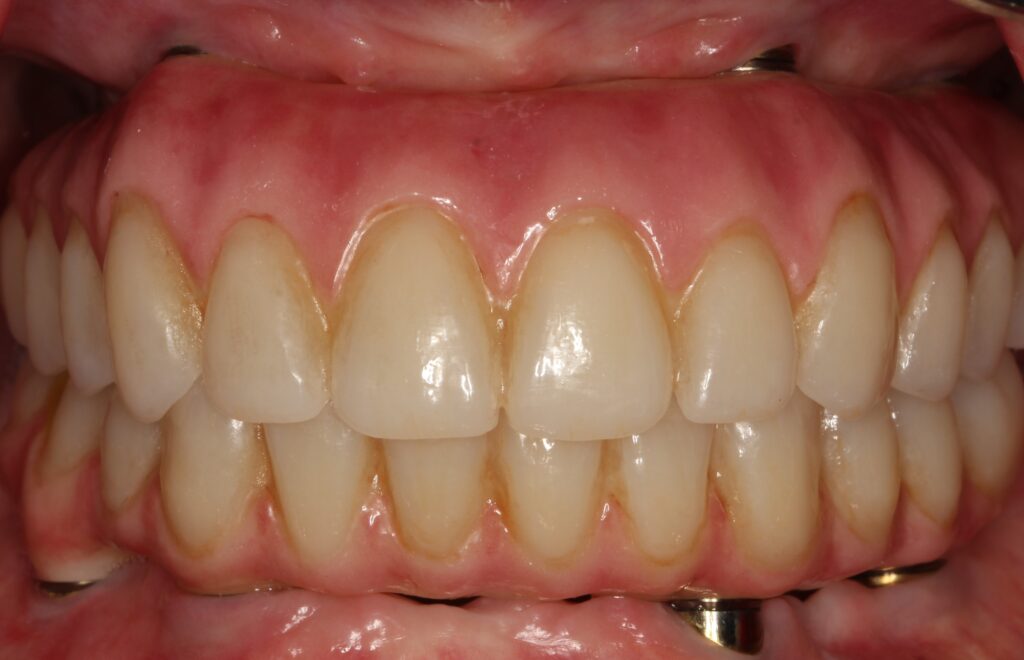

A selection of full arch fixed implant bridge patients after 5 years of wear